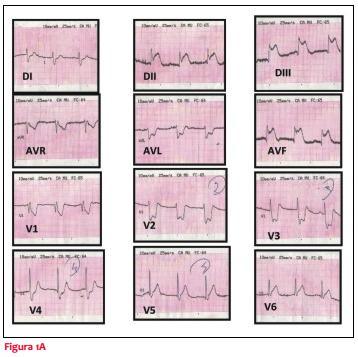

Hombre de 80 años con antecedentes personales de enfermedad pulmonar obstructiva crónica (EPOC), exfumador intenso, hipertensión arterial y apendicectomizado. Cuadro de infección respiratoria alta, bajo tratamiento antibiótico con amoxicilina en la última semana. Consulta a emergencia prehospitalaria por disnea sibilante, de reposo, brusca, acompañada de dolor precordial opresivo de tres horas de evolución. Concomitantemente agrega edema de cara, erupción y prurito cutáneo. Al examen físico, paciente lúcido, bien hidratado y perfundido, edema de párpados y labios, eritema a nivel de tronco y miembros superiores, a nivel cardiovascular ritmo regular de 60 cpm, ruidos bien golpeados sin soplos, no ingurgitación ni reflujo hepatoyugular, pulsos presentes en todos los territorios, presión arterial (PA): 90/60 mmHg, en lo respiratorio polipneico, murmullo alvéolo vesicular conservado, gemidos bilaterales. Resto del examen normal. Se realiza electrocardiograma (ECG) que evidencia disociación isoarrítmica y lesión subepicárdica de cara inferior (figura 1A).